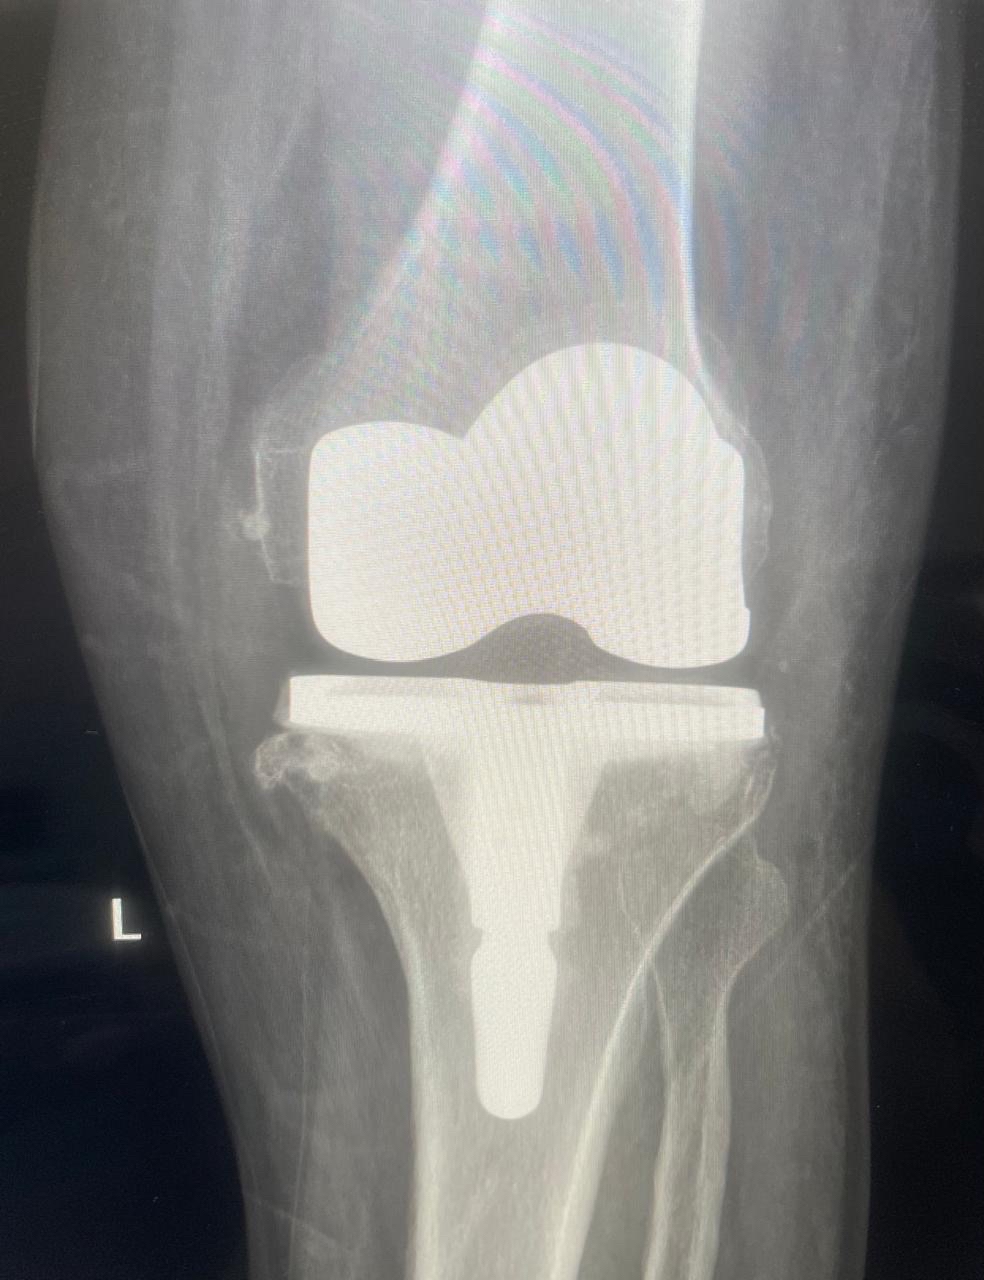

30 مريضاً يستعيدون الحركة بالقطيف.. ما تفاصيل الوحدة الجديدة؟

أعلن مستشفى القطيف المركزي إطلاق وحدة تخصصية لتبديل وترميم المفاصل، متوجاً انطلاقتها بإجراء 30 عملية جراحية ناجحة للركبة، لتعزيز كفاءة الرعاية الطبية وتطوير الخدمات وفق أحدث المعايير العالمية المعتمدة.

وأوضح المستشفى التابع لتجمع الشرقية الصحي، أن الوحدة الجديدة انضمت رسمياً للوحدات التخصصية بقسم العظام، مبيناً أن نجاح العمليات الثلاثين يعكس جاهزية الكوادر الطبية وتوفر التقنيات المتقدمة.

وبيّنت الجهات الطبية أن الوحدة تقدم منظومة رعاية متكاملة، تبدأ بتقييم وتشخيص دقيق لحالات تآكل المفاصل والإصابات المزمنة، وصولاً للتدخلات الجراحية المبتكرة.